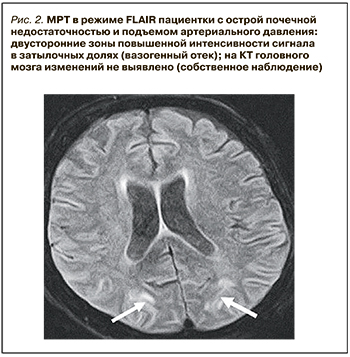

Активное применение КТ и МРТ позволило расширить представления о нейровизуализационных особенностях СЗОЭ. Так, к настоящему времени установлена возможность вовлечения в патологический процесс не только белого (лейкоэнцефалопатия), но и серого вещества головного мозга. Кроме классической локализации, изменения при СЗОЭ могут быть и в других отделах больших полушарий, подкорковых структурах, стволе и мозжечке (рис. 3) [10–12]. Значительно реже наблюдается односторонняя или асимметричная локализация СЗОЭ [13, 14]. Возможно также изолированное поражение ствола головного мозга или подкорковых структур без вовлечения классических зон [15, 16]. Кроме этого, показана возможность развития цитотоксического отека и ишемических изменений [9], микрокровоизлияний, внутримозговых и субарахноидальных кровоизлияний (рис. 4) [17]. Согласно данным Liman T.G. et al. [18], существует положительная связь между обширностью вазогенного отека головного мозга и вероятностью развития геморрагических осложнений.